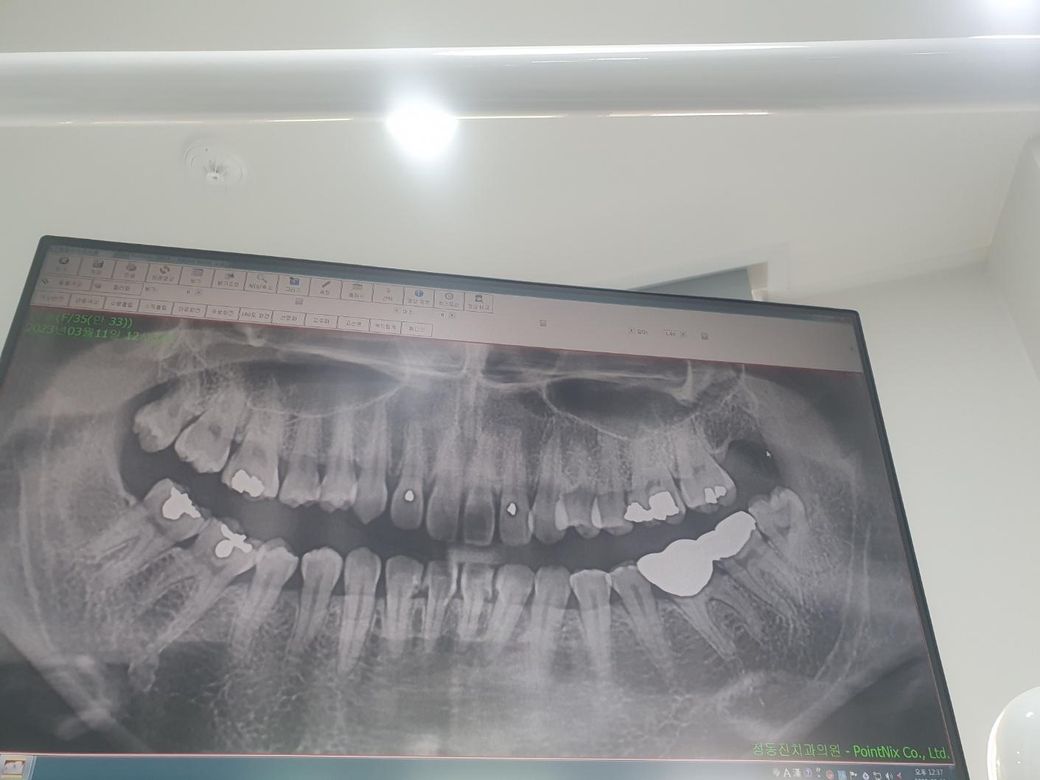

인접면충치 많이썩은거 맞죠??...

치과정기검진받는데 인접면충치치료받으라해서

타병원에 갔더니 아직 치료안해도된데요

그래서 또다른병원갔더니 치료하랍니다..머이리 말이다르고 제가봐도 많이썩고 이제 좀 아프기도한거같은데 아직치료안해도된다는 의사샘은 왜그러신걸까요?. .

• 1번 째 사진

인접면 우식이 관찰되며 치료를 받으셔야 할 것 같습니다. 왜 미루자고 했는지는 해댱 선생님께 여쭤봐야겠습니다.

파노라마 상으로도 인접면 충치가 잇어 보입니다 작은 엑스레이를 찍어보고 치료를 하시는게 좋을것같습니다.

위 파노라마 엑스레이 사진은 치아끼리 겹쳐서 부정확합니다. 치근단사진, 그 중에서도 교익방사선사진을 찍어봐야 인접면 충치가 제대로 평가됩니다.

현재 통증도 있고 사진상 충치가 진행이 된것으로 보이기에 치료를 권합니다.

한 병원에서는 치료를 빨리 시작하는 방침일 수 있고, 다른 병원에서는 보존적 치료를 우선시하여 충치가 더 진행된 후에 치료하자는 방향을 택할 수 있어 병원마다 의견의 차이가 있을수 있습니다.